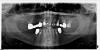

*Lena Опубликовано 23 ноября, 2010 Поделиться Опубликовано 23 ноября, 2010 Добрый день Уважаемые доктора! Неоднократно пользовалась Вашим форумом и советами, за что огромное спасибо. Окончание своей истории обязательно расскажу, как будут свежие снимки, а сейчас очень нужна помощь моей хорошей знакомой. Ей 61 год, снимок прилагается. Недавно сломался передний зуб (1, там где сейчас вкладка и временная коронка). Врач, взявшийся за протезирования 1, очень хотел привести весь рот в порядок, какой то сложной несъемной конструкцией (со слов знакомой) но увидев панарамный снимок, сказал что корни у зубов очень короткие, не смогут служить опорой и сказал, что необходимо удаление всех "крайних" зубов сверху (на них сейчас коронки-золото и мосты, зубы живые-большинство) и делать съемные протезы, внизу и вверху, и пока она не согласится на этот план лечения, постоянную коронку (МК) на вкладку он делать не будет. Теперь вопросы:1. Так ли необходимо все удалять и делать съемные протезы вверху, если никакого дискомфорта и "проблем" , кроме 1 зуба нету.2. Возможно ли все же на вкладку поставить постоянную коронку МК и верх пока больше не трогать?3. Возможно ли в таком возрасте внизу установить импланты? Насколько они будут надежны? (ширина десны-как выразился доктор, гребня, не большая). р.с. Никаких хронических заболеваний, препятствующих имплантации-нет, анализы крови хорошие. Женщина до сих пор работает! Самочувствие души и тела в норме , и очень уж не хочется съемный протез!Заранее огромное Вам спасибо! Очень ждем ответов. Ссылка на комментарий

Bier Опубликовано 23 ноября, 2010 Поделиться Опубликовано 23 ноября, 2010 тут 2 варианта - либо слепить центральный зуб из того что есть, и сколько простоит. либо удалить весь верх, т.к. ни одного приличного зуба там нет и сделать красивый полный съемный протез. Ссылка на комментарий

Bier Опубликовано 23 ноября, 2010 Поделиться Опубликовано 23 ноября, 2010 смысл безусловно есть, но что-то мне подсказывает (хотя по такому снимку с уверенностью этого не скажешь) что с имплантацией там не все так просто будет, но смысл есть. Ссылка на комментарий